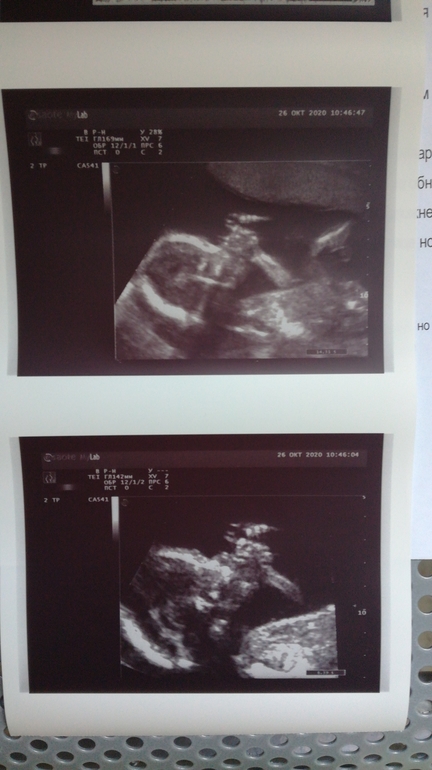

Нам в 16 недель на узи тоже фото с большим пальцем во рту сделали))Такие они карапузики смешные)Крохотные,а уже отрабатывают рефлексы)